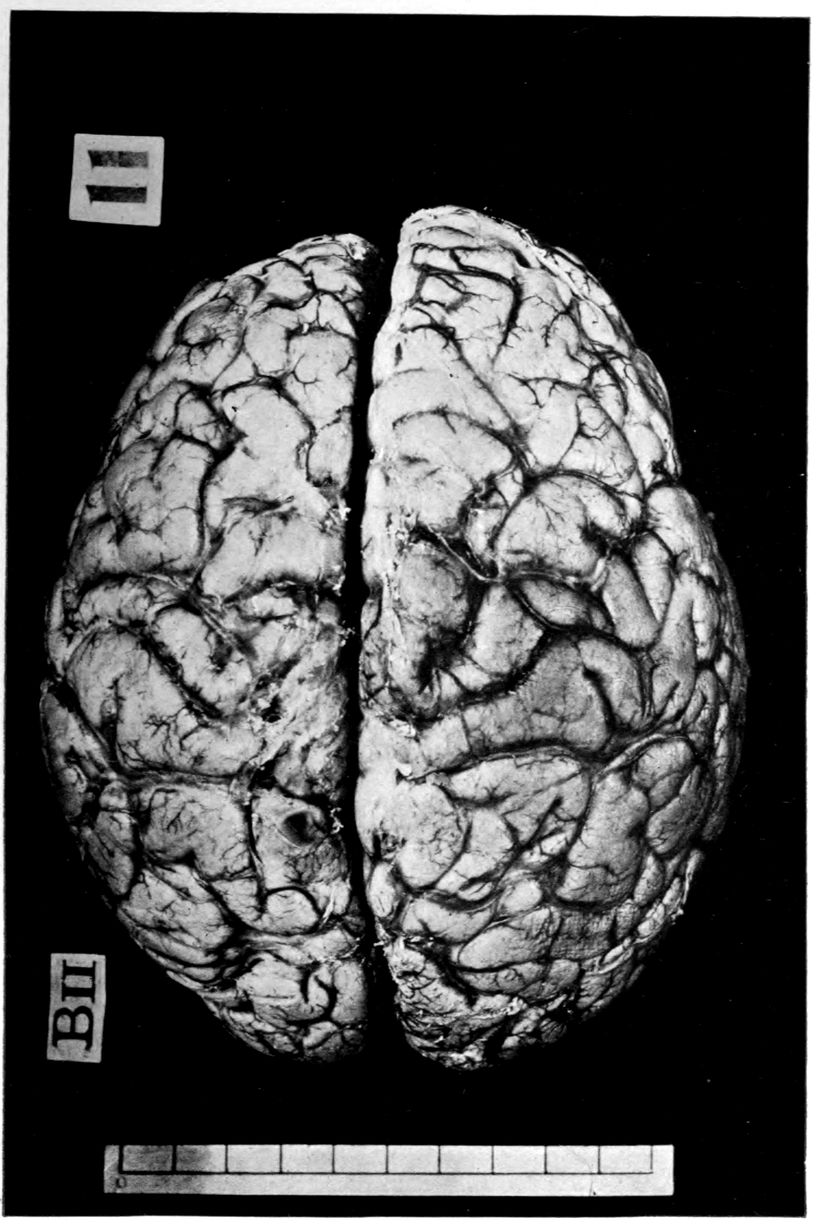

Case 4. James Pierce was an almshouse transfer to the Danvers Hospital in his fiftieth year. He died three years later. The accompanying brain pictures demonstrate so extensive a lesion of the left hemisphere that it is of great interest to determine if possible the genesis and course of his disease. It appears that syphilis had been acquired somewhere about the age of 38 or 40, so that the total duration of the process was between 13 and 15 years. In Pierce’s forty-third or forty-fourth year, he had a shock while walking in the streets of his native city, whereupon he was subsequently transferred to the Danvers Hospital, whose data have been summed up as follows (we are obliged to Dr. Charles T. Ryder for these data):

The autopsy findings were as follows:

Head: Calvarium of moderate thickness; diploë present; dura slightly adherent over bregmatic region. Longitudinal sinus contains cruor clot. Dura is somewhat thickened and slightly more opaque than normal. Pacchionian granulations, small but fairly numerous. Pia contains throughout a considerable excess of clear 44serous fluid. The convolutions in general are of good breadth and proportion. There is an atrophic area roughly circular in outline and about 2 cm. in diameter in the posterior part of the right third frontal convolution corresponding to Broca’s area on the opposite hemisphere. The space thus formed is filled with edema held by the pia. On the left side is a similar subpial collection which covers the site of the posterior portions of all of the third frontal convolutions, parts of the lower end of the precentral convolution, and the whole of the first temporal convolution, which have disappeared entirely. The basal vessels show slight changes.

Cerebellum and basal ganglia are grossly normal.

The spinal membranes are negative. The regions of the pyramidal tracts in the cord are firm, project slightly from surface of section, and are china white.

Summary: Here is a picture made up almost purely of Vascular Neurosyphilis, with Secondary Spinal (Pyramidal Tract) Changes. Doubtless the genesis of this picture is allied to that of Case 1 (Alice Morton) and to that of the terminal vascular complications in a tabetic, Case 2 (Francis Garfield).

The absence of meningeal and parenchymatous (i.e., outside the region of necrosis produced by the vascular disease) lesions is characteristic of an important group of neurosyphilitic diseases. It is clear that the case, although one of extensive lesions, is not one of diffuse lesions in the sense of Case 1 (Alice Morton).

Vascular neurosyphilis—effects of syphilitic thrombosis of Sylvian artery 10 years before death. (Case 4.)

Case 4. (See previous figure for brain lesion.) Three levels of the spinal cord showing unilateral pyramidal tract sclerosis, 10 years after cerebral thrombosis.